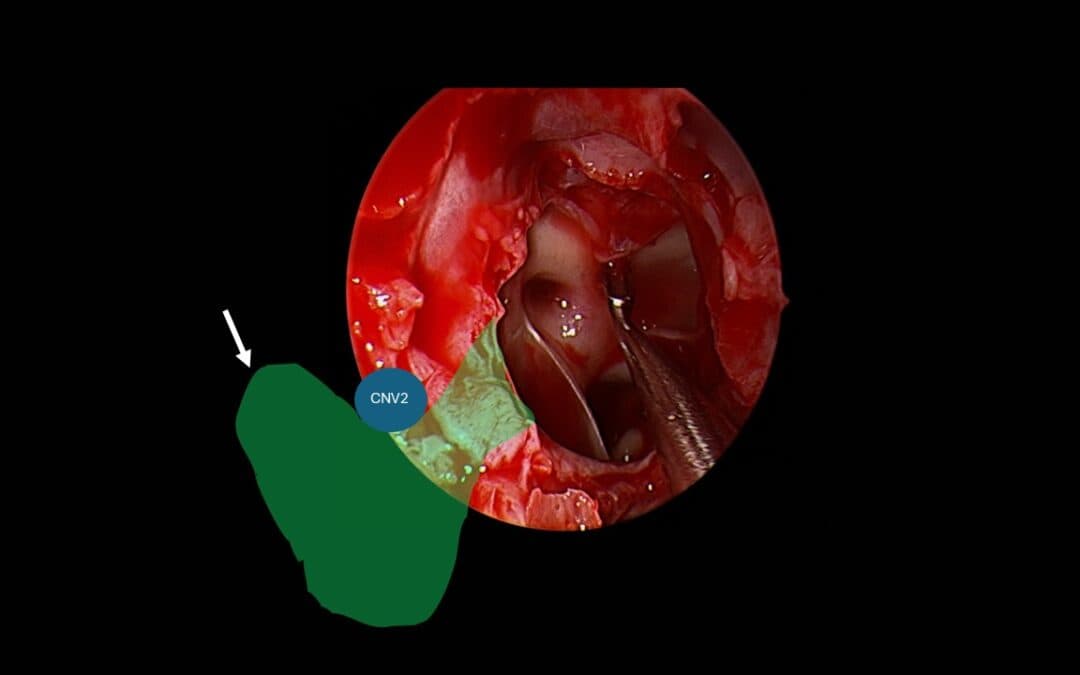

Lateral Sphenoid CSF Leak: Why the “Transpterygoid” Debate Misses the Real Surgical Question

by Richard Harvey | Mar 29, 2026 | Interesting articles on nose and sinus disease, Nose and Sinus Blog

Repairing a spontaneous nasal CSF leak in the lateral sphenoid is one of the more misunderstood operations in endoscopic skull base surgery. At a recent national meeting, I was struck by how often panelists used the term “transpterygoid approach” while clearly...